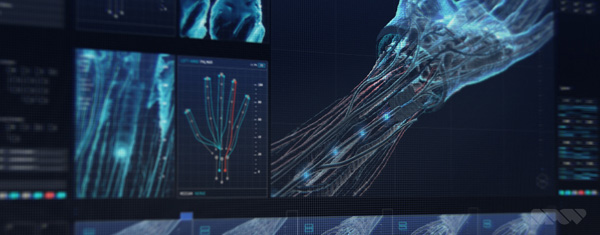

Nevertheless, instead of looking creepy or frightening, the results are strangely beautiful and pull the viewer toward the inner world of brains, bones and blood vessels. This look is no accident. SPOV’s main pipeline is based on Cinema 4D used together with After Effects for compositing – tools SPOV has used for years on nearly all projects and which nearly all of their artists are very familiar with.

Allen said, “For some of the artists here, Cinema 4D plus Creative Cloud software, mainly After Effects, sometimes Photoshop, are the means to create nearly anything. Over time, some have developed skills in 3D software like Maya, or ZBrush as a dedicated sculpting tool. But on ‘Doctor Strange’, although we needed diverse 3D effects, textures and modelling, only Cinema 4D and After Effects were used for everything, including a huge amount of detailed sculpting on some of the assets. We also successfully pushed Cinema’s Proximal Shader to create a smooth, adjustable ghosted effect.

“We could use soft, controllable Boolean operations for the ghosting of hard surfaces. In addition we could render out and animate a black-and-white map precisely determining the cut away areas. Passes were rendered and exported from Cinema 4D, and then layered up in After Effects for compositing.” A nice example of how this looks in the film is in the images above and at the top of this article, showing a portion of the skull cut away to reveal the brain inside.